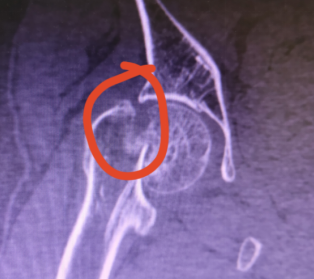

关节外科和创伤骨科收治较多的是股骨颈骨折的患者。

关节外科和创伤骨科收治较多的是股骨颈骨折的患者。股骨颈骨折是髋部较常见的损伤,是指由股骨头下至股骨颈基底部之间的骨折,是一种在老年人群中非常常见的骨折,骨折术后不愈合率及股骨头坏死发生率极高。

股骨颈骨折多数因行走跌伤时下肢扭转、内翻或外翻造成,受伤时多臀部着地,伤后髋部疼痛,不能站立和行走。路滑、路不平及上下台阶是骨折的诱发因素,骨质疏松是骨折的内在因素。股骨颈骨折大多数有比较明显的移位,骨折不稳定,因此需要住院手术治疗。